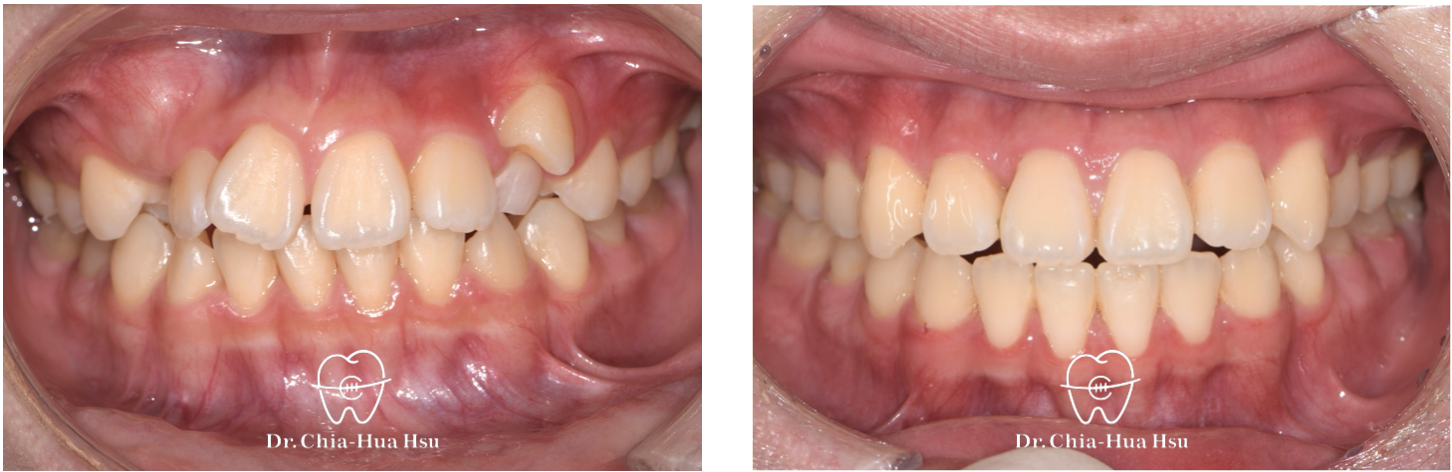

治療前

治療後